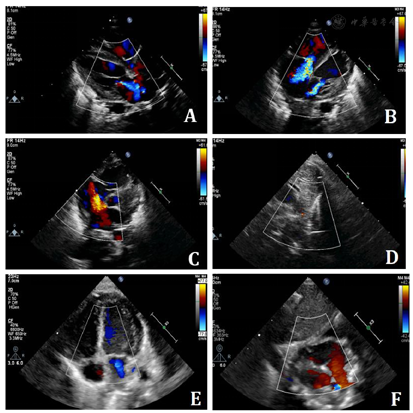

心电图提示:窦性心动过速;T波改变。床旁超声心动图:1.升主动脉于主动脉弓起始段(弓部内径约0.6cm)发出上位动脉弓和下位动脉弓两大分支,上位动脉弓分出头臂干、左颈总动脉、左锁骨下动脉后,多切面探查为盲端;下位动脉弓下行延续为降主动脉并降段狭窄,狭窄处内径约0.1cm,降主动脉起始段狭窄后扩张,内径约0.9cm。CDFI示降主动脉狭窄处血流速度增快,峰速3.1m/s,压差36mmHg(图1A、图1B);2.全心增大,左、右室室壁运动弥漫性减弱。另房间隔中部见一宽约0.66cm连续中断。二、三尖瓣形态、开放可,闭合不佳。CDFI:房间隔连续中断处见左向右为主的双向分流信号;降主动脉与左肺动脉见可见一细束左向右分流信号;二尖瓣口收缩期左房侧见中量反流信号;三尖瓣口收缩期右房侧见中至大量反流信号(图2A、图2B)。超声心动图显像提示:复杂先天性心脏病:1.主动脉弓发育异常永存第五主动脉弓(B型)并降主动脉缩窄;2.第四主动脉弓离断;3.房间隔缺损(左向右为主的双向分流);4.动脉导管未闭(即将闭合);5.二尖瓣中度关闭不全三尖瓣中至重度关闭不全;6.全心增大左、右室收缩功能测值减低;7.重度肺高压。